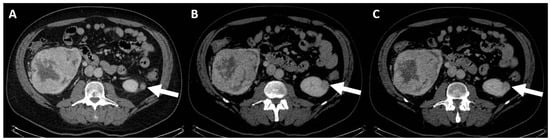

- (b) Class II: benign cyst, “minimally complex”, which includes 6 types in CT examination (Figure 3), all represented by well-defined masses with thin (≤2 mm) and smooth walls [95], and these include the following:

- Masses with thin walls (≤2 mm) and from one to three septa with possible enrichment of the septa and the wall, with the possible presence of calcifications of all types;

- Homogeneous masses with high density (≥70 HU) on non-contrast scan;

- Homogeneous masses with density >20 HU, which do not enhance and may have calcifications of all types;

- Homogeneous masses with density between −9 and 20 HU on non-contrast CT;

- Homogeneous masses with density between +21 and +30 HU at portal phase;

- Homogeneous masses with low density and too small to be characterized.